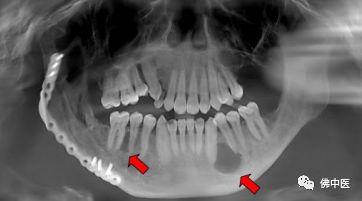

患者阿成X光片:箭头所指阴影位置为囊肿部位及范围

两例病例的主要特点是颌骨多发囊肿。患者阿芳和阿成两人都是在觉得口腔内黏膜逐渐肿起来时才到口腔科就诊。阿芳到我院就诊后,才发现自己上下颌骨的骨头内长了十几个囊肿。而阿成2年前已经诊断患有基底细胞痣综合征,这次在定期复查中复查发现囊肿又长出来了。